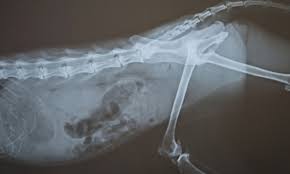

How To Diagnose Colon Cancer In Dogs : Colorectal Cancer In Young People Man 23 Has Stage 4 Cancer : As most people like dogs more than humans, giving dogs the best care is a priority, including being on the lookout for signs of cancer.. Less often, part of the colon may need to be surgically removed to make the diagnosis. What are the different types of imaging techniques used to diagnose cancer in cats and dogs? In dogs the most common sites for instestinal tumors are the colon and the rectum. Now more than ever, it's critical to know the signs of cancer. The warning signs of cancer in dogs are very similar to that in people.

Clinical diagnosis if your vet believes colon cancer may be the root of your pet's health issues, he will conduct a physical exam and laboratory tests to reach a definitive diagnosis. In dogs the most common sites for instestinal tumors are the colon and the rectum. Diagnosis you will need to provide a thorough history of your dog's health leading up to the onset of symptoms. If your dog collapses, get to the vet immediately. In a biopsy, the doctor removes a small piece of tissue with a special instrument passed through the scope.

Pin By Bea Rudd On Dogs The Holistic Approach To Dog S Health R Cat Care Tips Rectal Cat Care from i.pinimg.com Adenosarcoma is diagnosed when the tumor(s) grow from the apocrine glands located on each side of the rectum. In dogs the most common sites for instestinal tumors are the colon and the rectum. Two types of colon cancer exist in dogs: Diagnosing colon cancer in dogs a veterinarian, after completing a history of the dog's symptoms and a physical exam, will feel or palpitate the dog's abdomen and order blood samples from the dog to be evaluated to start. This can happen when there is a high suspicion of cancer, for example, an enlarged spleen in a dog who is not acting right. Clinical signs of intestinal cancer are weight loss, loss of appetite, vomiting, diarrhea and blood in vomit or feces. the usual clinical signs of intestinal cancer are weight loss, loss of appetite, vomiting, diarrhea and blood in vomit or feces. Lymphoma/lymphosarcoma is diagnosed when the lymph nodes or lymphoid tissues in the gastrointestinal tract are affected. Certain breeds, such as collies and german shepherds, are more likely to develop adenocarcinoma.

Lumps and bumps underneath a dog's skin abnormal odors emanating from the mouth, ears or any other part of the body This can happen when there is a high suspicion of cancer, for example, an enlarged spleen in a dog who is not acting right. Clinical diagnosis if your vet believes colon cancer may be the root of your pet's health issues, he will conduct a physical exam and laboratory tests to reach a definitive diagnosis. Diagnosis you will need to provide a thorough history of your dog's health leading up to the onset of symptoms. Less often, part of the colon may need to be surgically removed to make the diagnosis. Your veterinarian will perform a complete physical examination on your dog, with blood tests, fecal tests and a biochemistry profile. Cancer is a terrifying reality for dog owners today, causing nearly half the deaths of dogs over the age of 10. On the other hand, leimyosarcomas and gastrointestinal stromal tumors normally originate in the cecum (first part of the small intestine). As most people like dogs more than humans, giving dogs the best care is a priority, including being on the lookout for signs of cancer. Manual palpation or probing of the stomach is a common first step, followed by a rectal examination. Diagnosis screening for colon cancer. The american veterinary medical association (avma) reports that one in four dogs will develop cancer at some time in their life and that 50% of pets over the age of 10 will develop cancer. Screening has been shown to reduce your risk of dying of colon.

In order to formally diagnose or rule out colon cancer in your dog, your vet will need to perform a range of tests as well as taking into account your dog's history, and a thorough physical examination. In addition, there is the instance of chronic episodic colitis. Diagnosing colon cancer in dogs a veterinarian, after completing a history of the dog's symptoms and a physical exam, will feel or palpitate the dog's abdomen and order blood samples from the dog to be evaluated to start. Lymphoma/lymphosarcoma is diagnosed when the lymph nodes or lymphoid tissues in the gastrointestinal tract are affected. Finding colon cancer at its earliest stage provides the greatest chance for a cure.

Don't be afraid to call your vet and ask for advice, a quick opinion or for your pet to be seen. Manual palpation or probing of the stomach is a common first step, followed by a rectal examination. Now more than ever, it's critical to know the signs of cancer. Dogs with gastrointestinal cancers, such as canine intestinal cancer or stomach cancer (gastric adenocarcinomas, gastric leiomyosarcoma) are usually male and 10 years of age or older. Diagnosing colon cancer in dogs a veterinarian, after completing a history of the dog's symptoms and a physical exam, will feel or palpitate the dog's abdomen and order blood samples from the dog to be evaluated to start. In order to formally diagnose or rule out colon cancer in your dog, your vet will need to perform a range of tests as well as taking into account your dog's history, and a thorough physical examination. Some commonly refer to the disease as belly or abdominal cancer. Finding colon cancer at its earliest stage provides the greatest chance for a cure. Lymphoma/lymphosarcoma is diagnosed when the lymph nodes or lymphoid tissues in the gastrointestinal tract are affected. A lump or a bump, a wound that doesn't heal, any kind of swelling, enlarged lymph nodes, a lameness or swelling in the. However, the following list identifies some of the most common signs of cancer in dogs: In dogs the most common sites for instestinal tumors are the colon and the rectum. Affected dogs are usually diagnosed between 9 and 12 years of age.53 hsa tends to affect large breed animals more often than smaller ones.

Some dogs will have additional symptoms of vomiting, weight loss, lethargy, and dehydration, depending on the illness. Doctors recommend certain screening tests for healthy people with no signs or symptoms in order to look for signs of colon cancer or noncancerous colon polyps. In a biopsy, the doctor removes a small piece of tissue with a special instrument passed through the scope. Two types of colon cancer exist in dogs: In order to formally diagnose or rule out colon cancer in your dog, your vet will need to perform a range of tests as well as taking into account your dog's history, and a thorough physical examination.

Your veterinarian will perform a complete physical examination on your dog, with blood tests, fecal tests and a biochemistry profile. With pets living longer than ever, cancer has become a diagnosis that we see more commonly in older dogs. Signs of cancer in dogs may vary greatly depending upon a number of factors. Lumps and bumps underneath a dog's skin abnormal odors emanating from the mouth, ears or any other part of the body The warning signs of cancer in dogs are very similar to that in people. The hardest thing about diagnosing cancer in a dog or cat is that it manifests in symptoms that are so broad and across the spectrum. Two types of colon cancer exist in dogs: Adenosarcoma is diagnosed when the tumor(s) grow from the apocrine glands located on each side of the rectum. What are the different types of imaging techniques used to diagnose cancer in cats and dogs? In addition, there is the instance of chronic episodic colitis. As most people like dogs more than humans, giving dogs the best care is a priority, including being on the lookout for signs of cancer. Collapsing, weakness, and general lethargy (not greeting people at the door like usual or less interaction) are common signs of cancer, says jake. In a biopsy, the doctor removes a small piece of tissue with a special instrument passed through the scope.